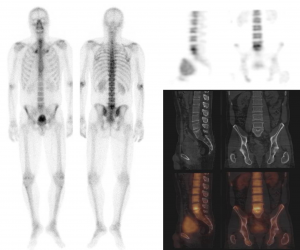

Skeletscintigrafie oftewel botscan

De naam zegt het al; bij dit type scan worden botten en gewrichten in beeld gebracht. Met een zogeheten gammacamera en gebruikmaking van een kleine hoeveelheid radioactieve stof worden beelden gemaakt van het skelet, eventuele afwijkingen worden zo letterlijk aan het licht gebracht.

Tijdens het maken van de scan lig je op een onderzoeksbed, de gammacamera is boven en/of onder je. Het apparaat -dat indrukwekkend groot is- vangt de straling van de radioactieve stof op, waardoor een beeld van je skelet ontstaat. Zoals bij ieder type scan is het van groot belang om goed stil te liggen.